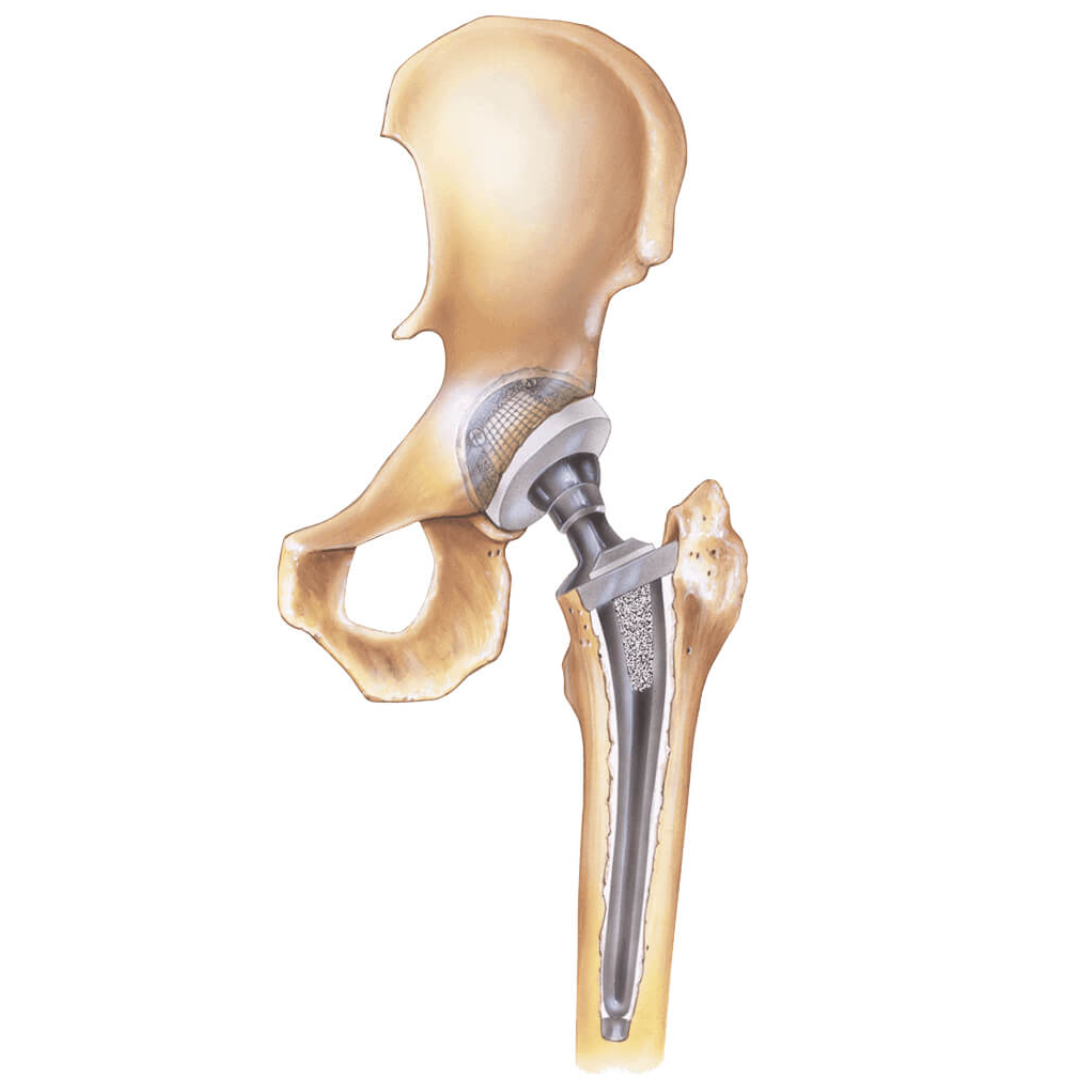

La prótesis total de cadera es un procedimiento en el que se reemplazan las superficies dañadas de la articulación por componentes metálicos y de polietileno de alta durabilidad.

Se retira el cartílago y hueso deteriorado.

Se colocan componentes que recrean la forma natural de la rodilla.

Se equilibran los ligamentos para brindar estabilidad y movimiento fluido.